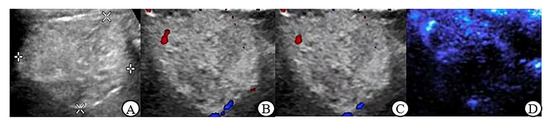

3.3. CDFI, PDI and MFI Evaluation of Blood Flow Characteristics in Benign and Malignant Renal Tumors ≤ 4 cm

3.5. Peripheral Blood Flow Characteristics of Renal Tumor in MFI Mode